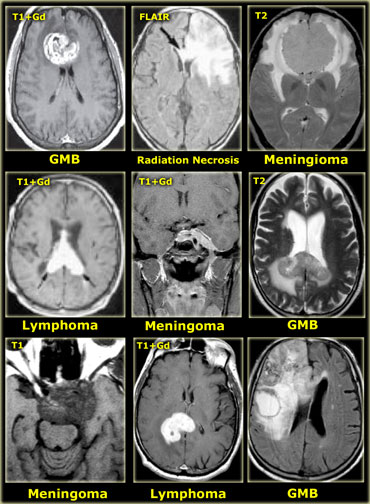

Tumors and tumor-like masses that cross the midline Tumors and tumor-like masses that cross the midline

Midline crossing

The ability of tumors to cross the midline limits the differential diagnosis.

• Glioblastoma multiforme (GBM) frequently crosses the midline by infiltrating the white matter tracts of the corpus callosum.

• Radiation necrosis can look like recurrent GBM and can sometimes cross the midline.

• Meningioma is an extra-axial tumor and can spread along the meninges to the contralateral side.

• Lymphoma is usually located near the midline.

• Epidermoid cysts can cross the midline via the subarachnoid space.

• MS can also present as a mass lesion in the corpus callosum.